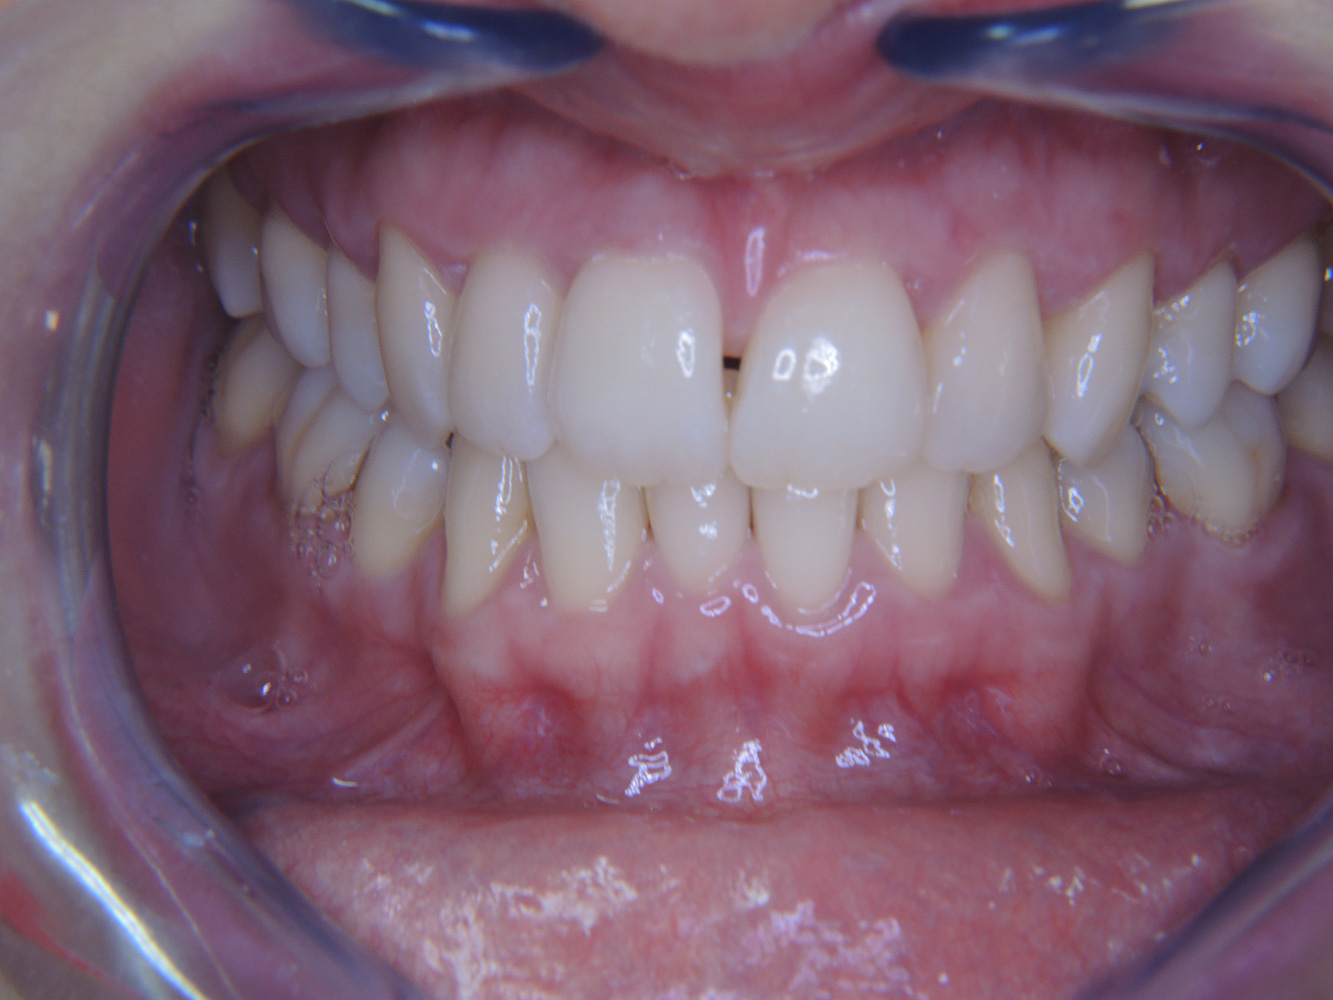

The healthy patient with early periodontal disease

The 68-year-old patient has no general health conditions and is not taking any medication that may be relevant to her oral health, and her lifestyle does not pose any particular risk. The patient has two dental implants (3rd quadrant, for five years) and a previous case of periodontal disease (stage IV, grade B periodontitis) with tooth loss. Currently the periodontal conditions are stable. However, periodontitis significantly increases the biological complications of implantations and there is a risk of implant loss (21). Four recommendations can be determined for the prophylaxis session. more